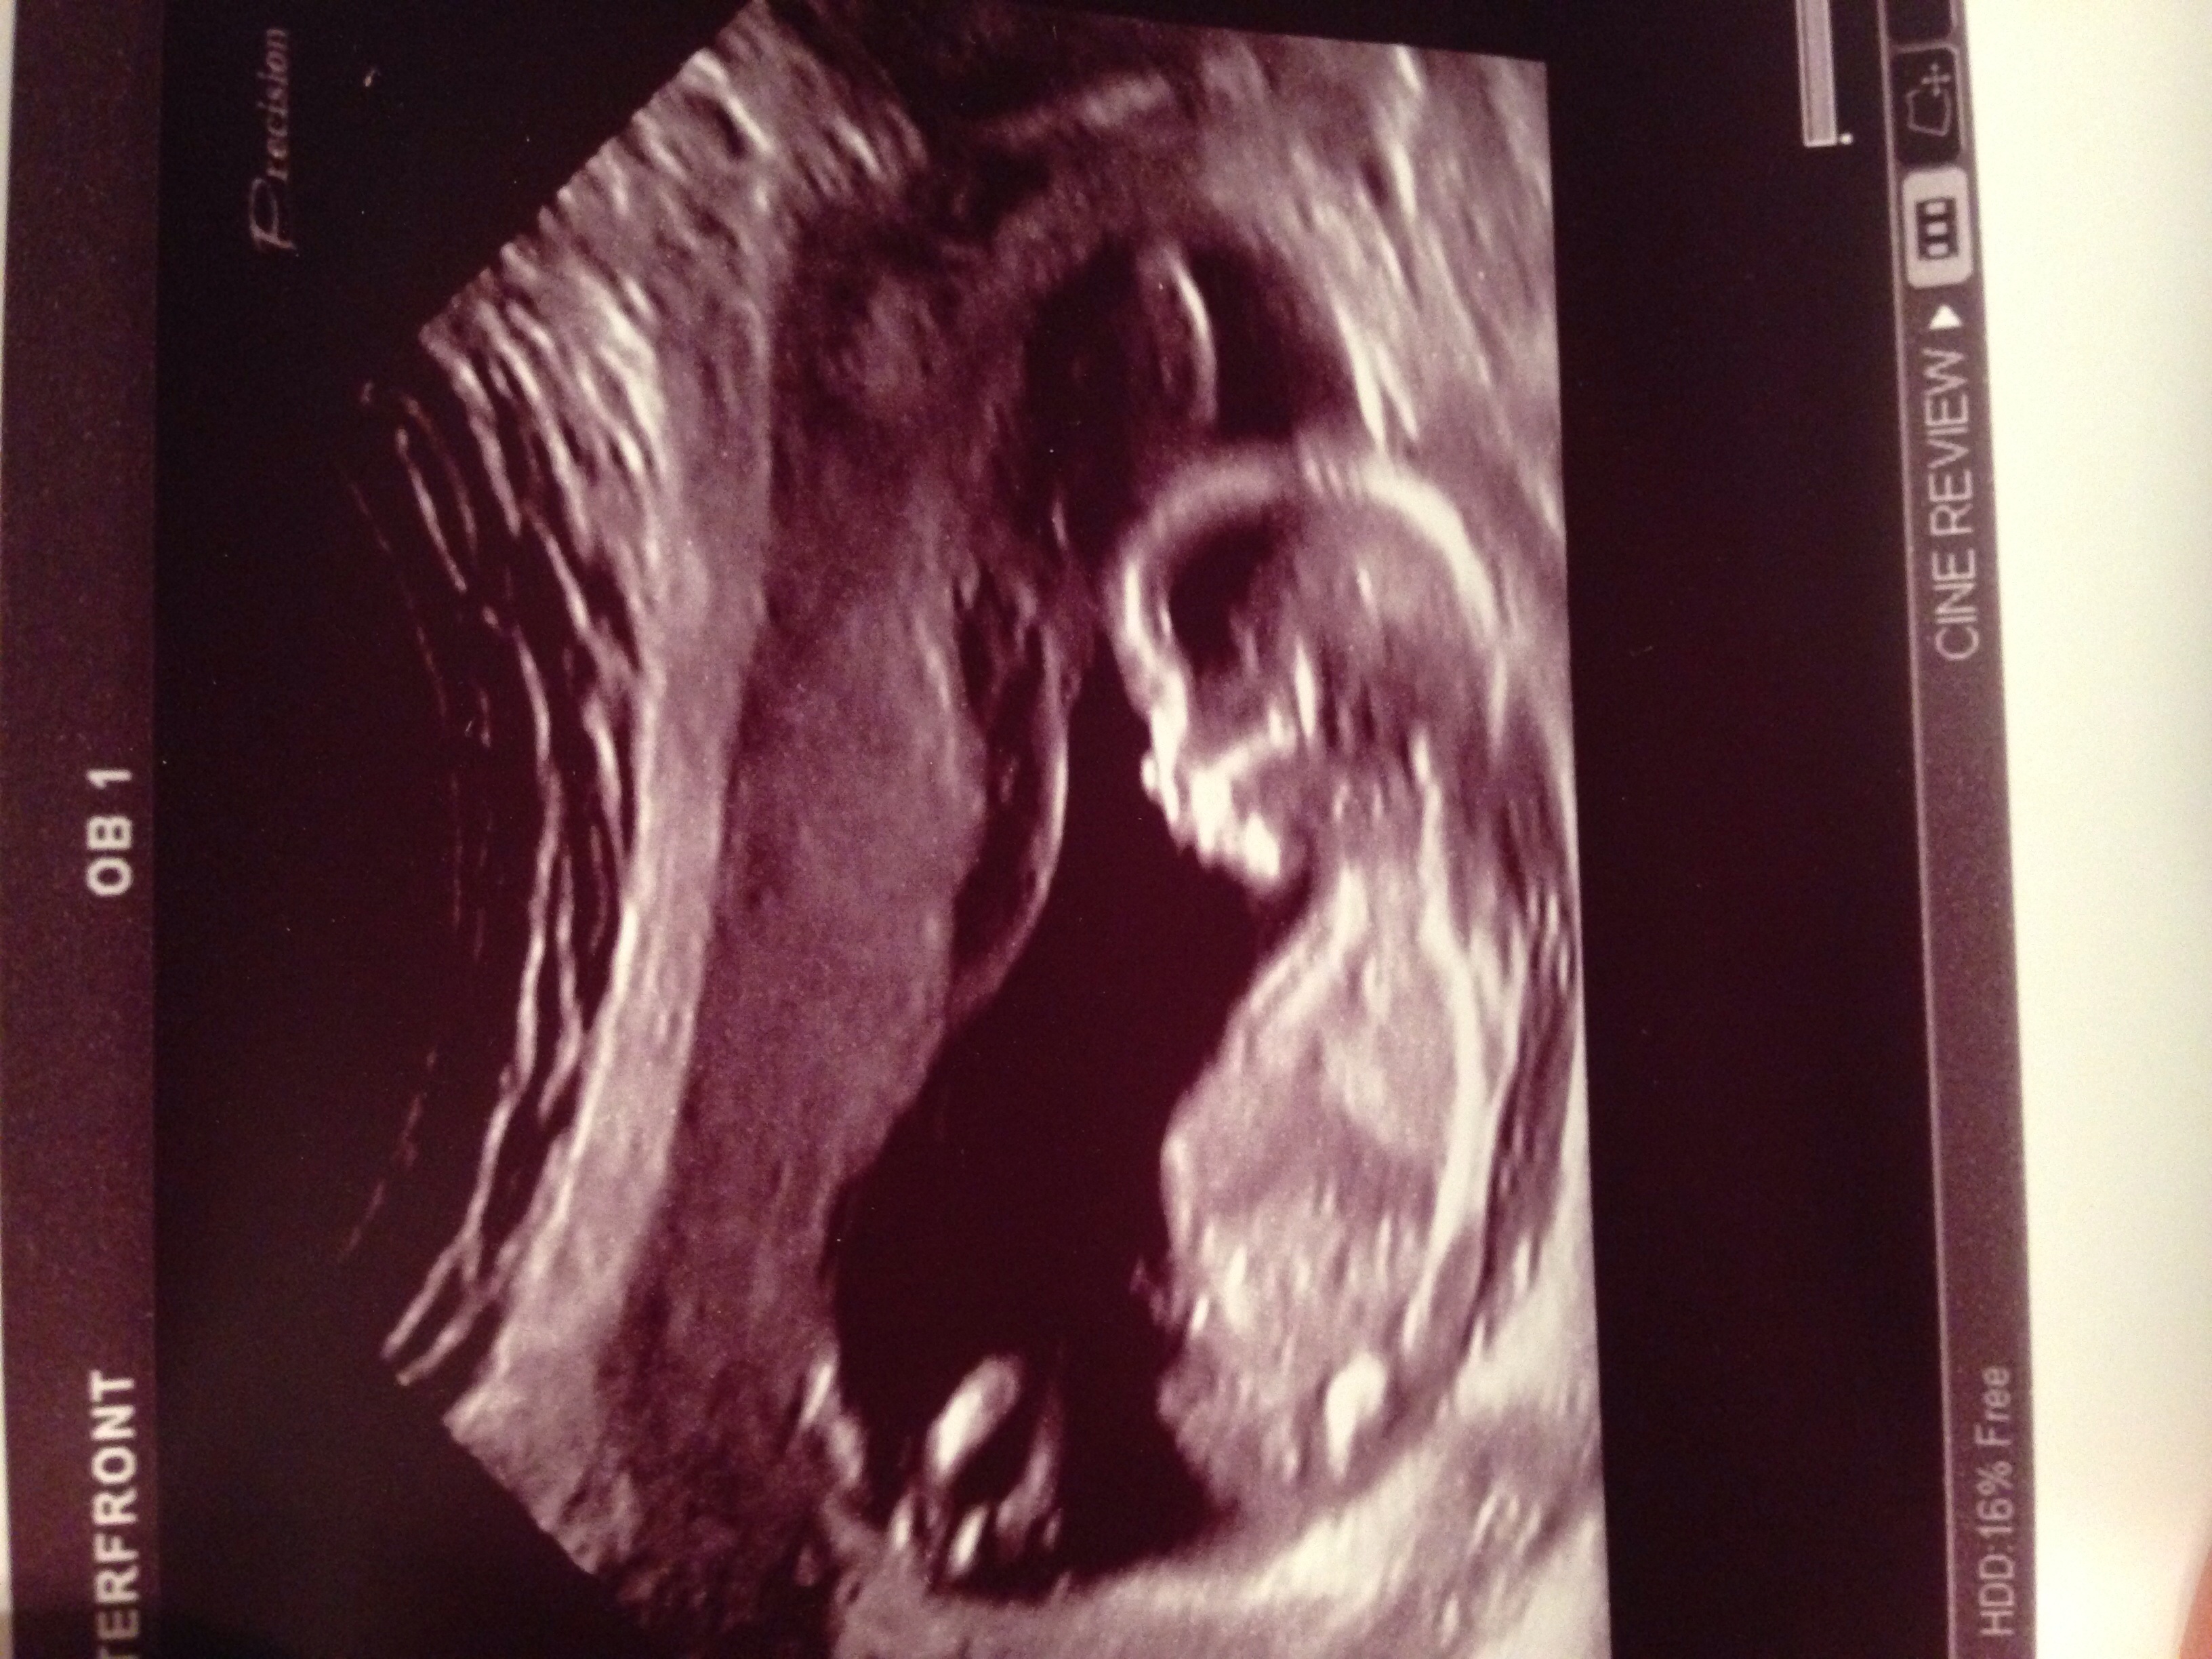

I'm not sure if any of these pictures have any gender clues, but could you please take a look and guess?! Thank you!!

But going by your pics... the first 2 aren't definitive, the 3rd looks very girly and the 4th looks sort of boyish.